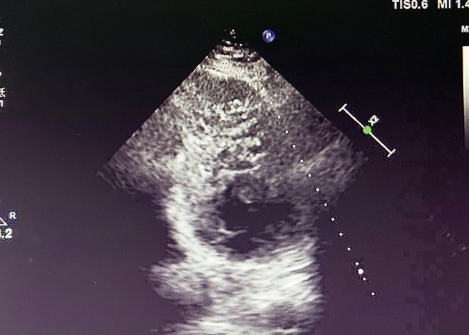

入院后,患者接受超聲心動(dòng)圖檢查,結(jié)果顯示左心室心肌呈典型 “海綿樣” 改變,可見多發(fā)、粗大的肌小梁和深陷的隱窩,非致密化心肌層與致密化心肌層比值(NC/C)>2.3,完全符合左心室心肌致密化不全(LVNC)的超聲診斷標(biāo)準(zhǔn)。

LVNC 的超聲表現(xiàn)

(1)特征性表現(xiàn)左心室壁明顯增厚,內(nèi)層心肌呈 “網(wǎng)狀” 疏松結(jié)構(gòu),外層致密心肌變薄,血流灌注顯示隱窩內(nèi)血流緩慢,這種情況容易形成血栓。(2)診斷標(biāo)準(zhǔn)(Jenni 標(biāo)準(zhǔn))收縮末期非致密化心肌層與致密層厚度比 > 2,可見深陷的肌小梁間隱窩與心室腔交通。